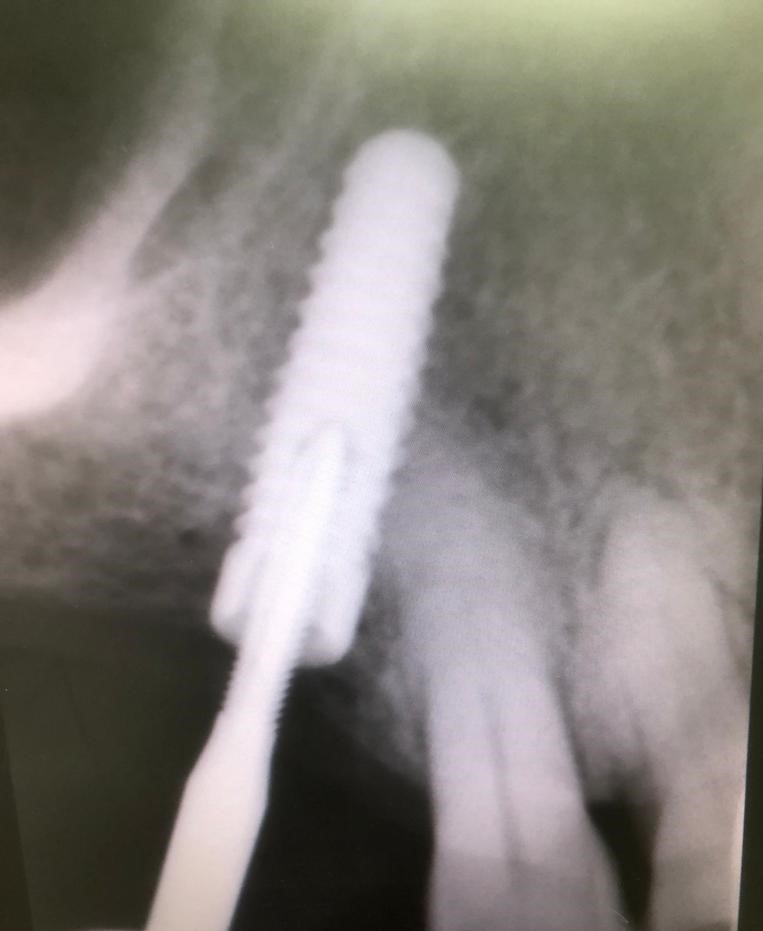

En realidad, lo más notorio de este caso es el uso por primera vez de un tornillo pasante mucho más sofisticado fabricado y distribuido por la empresa Suministros ASATIM. Este tornillo pasante es especial porque está fabricado en cromo-cobalto recubierto de nitruro de titanio. Esto le imprime una gran biocompatibilidad. Y también, al ser aleación de cromo-cobalto presenta mucha más resistencia a la fractura que si estuviera fabricado en aleación de titanio. De hecho el límite de elasticidad de la aleación de cromo-cobalto es el doble al límite de elasticidad de la aleación de titanio.

Queremos resaltar que es mucho más importante el límite de elasticidad de un metal que la resistencia a la fractura de dicho metal, ya que el límite de elasticidad es el que marca la verdadera resistencia a la fractura. Ambos coeficientes son directamente proporcionales.

Con la instalación de este tornillo esperamos una mayor durabilidad de la restauración protésica. Este nuevo tornillo pasante fabricado con unas métricas muy ajustadas al plano mejora la adaptación a las roscas de los implantes. Apostamos por esta nueva tecnología en el tratamiento de nuestros pacientes y con ello esperamos mejorar los resultados de las prótesis sobre implantes.